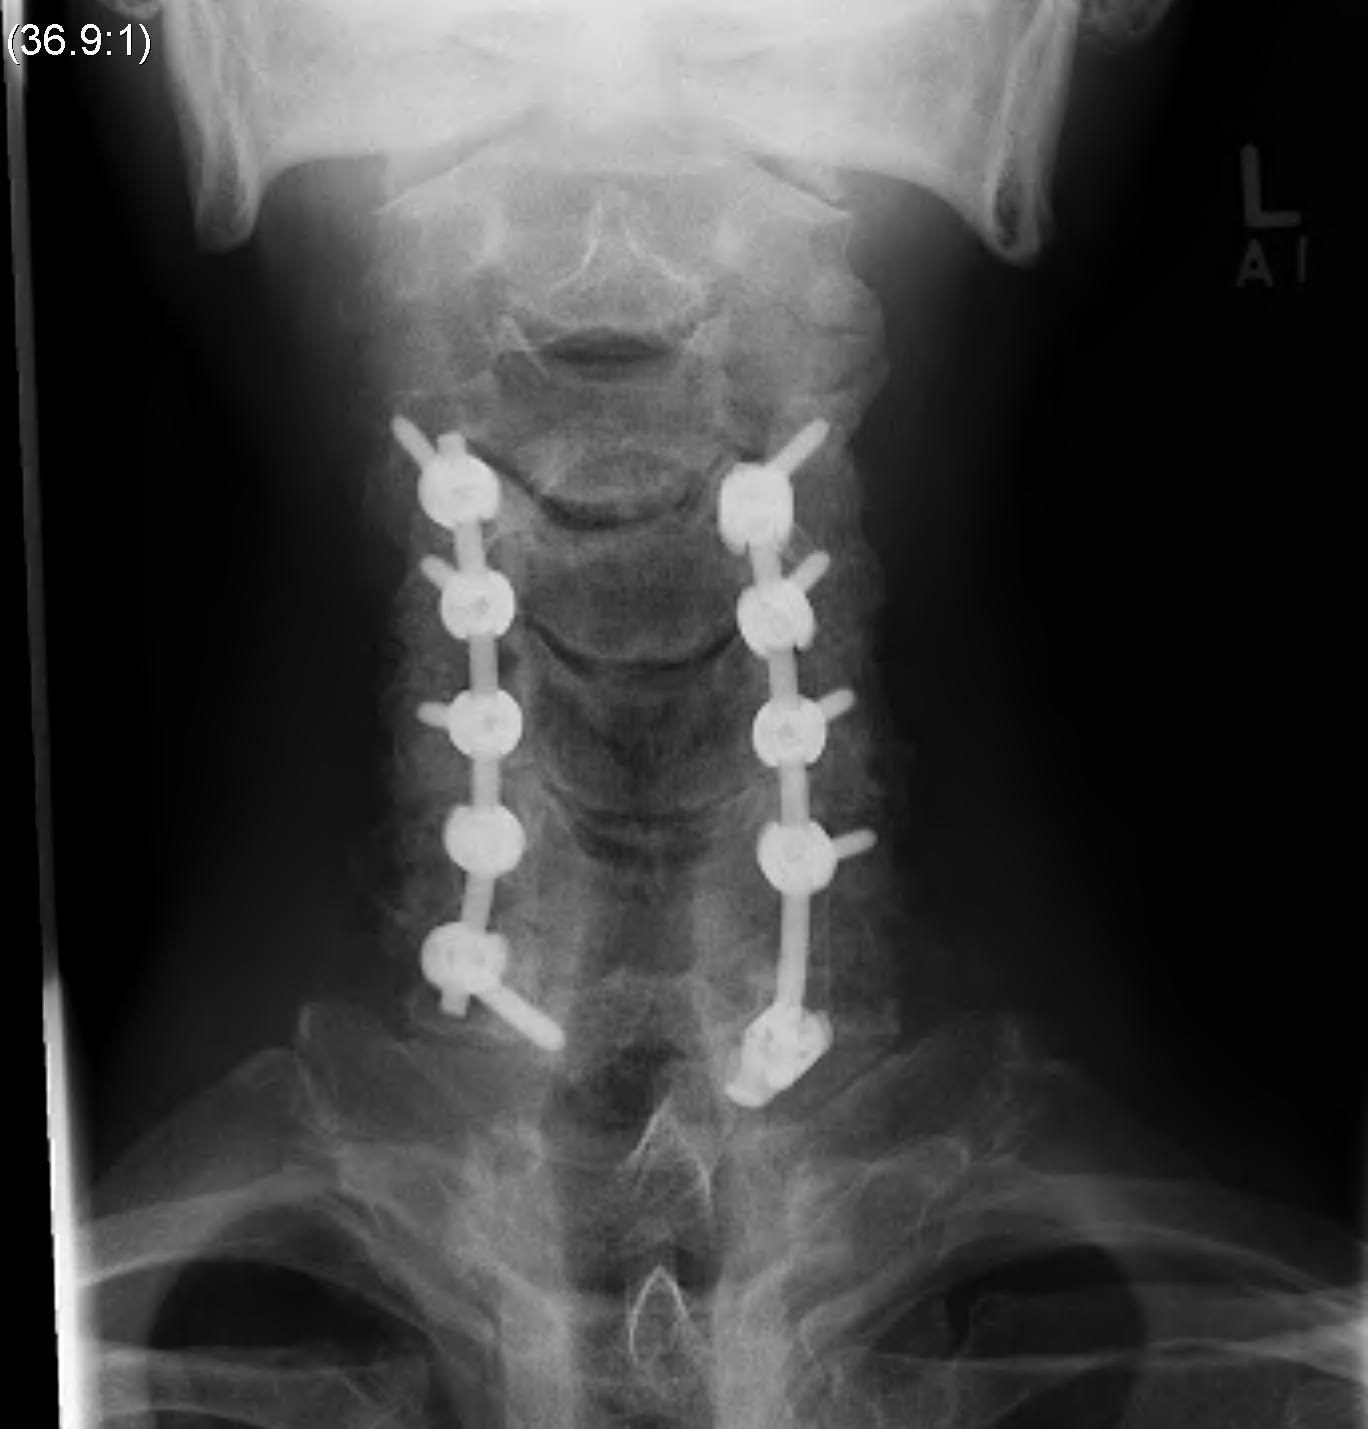

Laminectomy and Fusion

Concept

Posterior decompression is an indirect technique

- requires posterior shifting of the cord in the thecal sac

Indications

Lordotic cervical spine / no kyphotic deformity

Ossification of PLL

- dura may be adhered

- high risk of irreparable dural tears with anterior approach

Technique

Posterior approach

- prone

- Mayfield head tongs in neutral

- protect eyes / elbows (ulna nerve) / knees (CPN)

- pneumatic compression stockings

- IDC

- infiltration of skin with adrenaline solution

Decompression

- wide laminectomy +/- foraminotomy

Instrumentation

- avoids progressive kyphotic deformity

- lateral mass screws